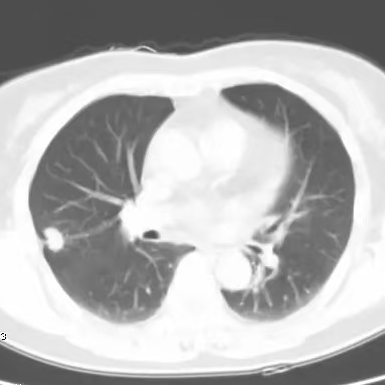

健康直通车: 健康是生命的宝贵财富,也是幸福生活的基石。为了更好地服务广大百姓,传播健康知识,葫芦岛市第二人民医院推出“健康直通车”专题栏目,将专业的医学知识以通俗易懂的方式传递给每一位市民,掌握科学的疾病预防方法,共同构筑健康中国的坚实基石。 什么是肺结节 肺结节是指肺内直径小于或等于3cm的类圆形或不规则形病灶,影像学表现为密度增高的阴影。大于3cm的称肿块。肺结节依其密度不同可分为实性结节、部分实性结节、磨玻璃结节,其中部分实性结节的恶性可能性最大,磨玻璃结节次之,实性结节尤其是小的实性结节结节最可能是良性的。 肺结节的常见病因 1、良性(约90%) 🔸 感染:结核、真菌、细菌性肺炎后遗留的瘢痕; 🔸 非感染:错构瘤(良性肿瘤)、炎性假瘤、血管瘤等。 2、恶性(约10%) 🔸原发性肺癌(如腺癌、鳞癌); 🔸转移性肿瘤(其他器官癌症转移至肺)。 如何根据影像判断肺结节性质 1、依据结节大小判断 🔸小于0.5cm的肺结节绝大多数都是良性的,属于微小结节。即使部分小于0.5cm肺结节是恶性的,但是适当的观察不影响预后。每年复查一次胸部CT就可以。 🔸大于0.5cm持续存在的纯磨玻璃结节,观察6个月,若持续存在,不管有无进展均多数是恶性的,视患者意愿,手术可以立即做也可观察至进展再做,不影响预后。 🔸大于0.8cm的部分实性结节恶性可能性非常大,应积极评估结节边缘毛刺、分叶、胸膜凹陷等征象。 🔸若实性部分大于0.5cm,恶性率显著提高。若在3~6个月随访期间实性部分增大或者总体部分增大,都可以考虑手术切除。而即使小于0.8cm的部分实性结节也需3个月就复查对比。 2、依据肺结节形态 如CT上提示病灶形态不规则、毛刺、分叶、胸膜凹陷、空泡征、血管集束征等,符合恶性肿瘤的征象。 🔸结节与正常肺组织之间界限非常清楚的恶性可能性大。 🔸结节密度不均呈混杂密度或均匀较大纯磨玻璃结节也基本是恶性的。 🔸有胸膜牵拉(不管是肺表面的脏层胸膜还是叶间裂部位的胸膜)的恶性可能性大。 🔸结节有浅分叶、细毛刺,密度较高而与周围肺组织边界不清的恶性可能性大。 🔸磨玻璃或混合磨玻璃结节存在小空洞的恶性可能性大。 🔸影像上似慢性炎表现,而没有炎症相关的其他异常,特别当所谓炎症区域内部或一侧与正常肺组织之间界限非常清楚的基本上是恶性的。 3、从结节发展情况来看 所有随访中增大进展的都需要考虑恶性可能,不进展而持续存在的纯磨玻璃结节也需考虑恶性。 葫芦岛市第二人民医院肺结节诊治中心孙振教授深耕肺结节领域四十余载,凭借对临床实践的执着钻研与深厚积淀,在肺结节精准诊断及鉴别诊断领域形成独到见解。他系统总结海量临床病例,创新性提炼出一套科学化、规范化的肺结节全周期诊疗体系,尤其在早期微小结节的影像特征识别、良恶性风险分层等方面积累了丰富经验,为众多患者提供了精准、高效的诊疗方案。 人民医院·人民名医 孙振 主任医师 三级教授 ·葫芦岛市第二人民医院胸外科主任、肺结节诊治中心主任 ·中国医科大学客座教授 ·原央企总医院著名胸外科专家 ·辽宁省医学会胸外科委员 ·辽宁省抗癌协会肺癌专业委员会委员 ·辽宁省细胞生物学学会食管癌专业委员会理事 ·主持多项科研成果获科技成果奖、科技进步奖、国家专科奖项 医学成就 从事胸外科临床工作近40年,担任胸外科首席专家及科室主任20余年,是我省胸外科领军人物,推动肺癌、食管癌等胸部肿瘤外科的规范化诊疗,在央企总医院牵头成立了肺结节诊疗中心,率先开展CT引导下肺内小结节定位切除,既确切完整切除肺内小结节,又降低肺功能损害。 专业特色 擅长肺癌、食管癌的外科手术和综合治疗,在各类高难度胸外伤手术治疗、胸腔镜微创手术、胸腺瘤手术及复杂并发症处理方面具有高深造诣,尤其擅长肺癌早期诊断,胸部小结节CT早期肺癌的鉴别等。完成各类高难度胸外科手术5000余例,其中微创手术占比达90%,治愈率达98%,多项业务填补省内空白。 开展的高难手术 胸腔镜肺部结节微创手术、肺癌根治术、食管癌根治术、各种纵隔肿瘤切除术、胸骨后甲状腺手术及胸部复合性外伤的抢救手术等。